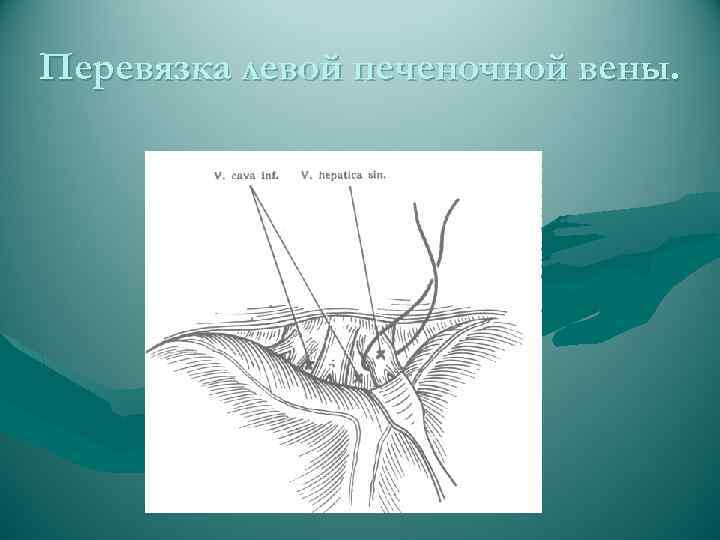

Перевязка левой печеночной вены.

Перевязка левой печеночной вены.